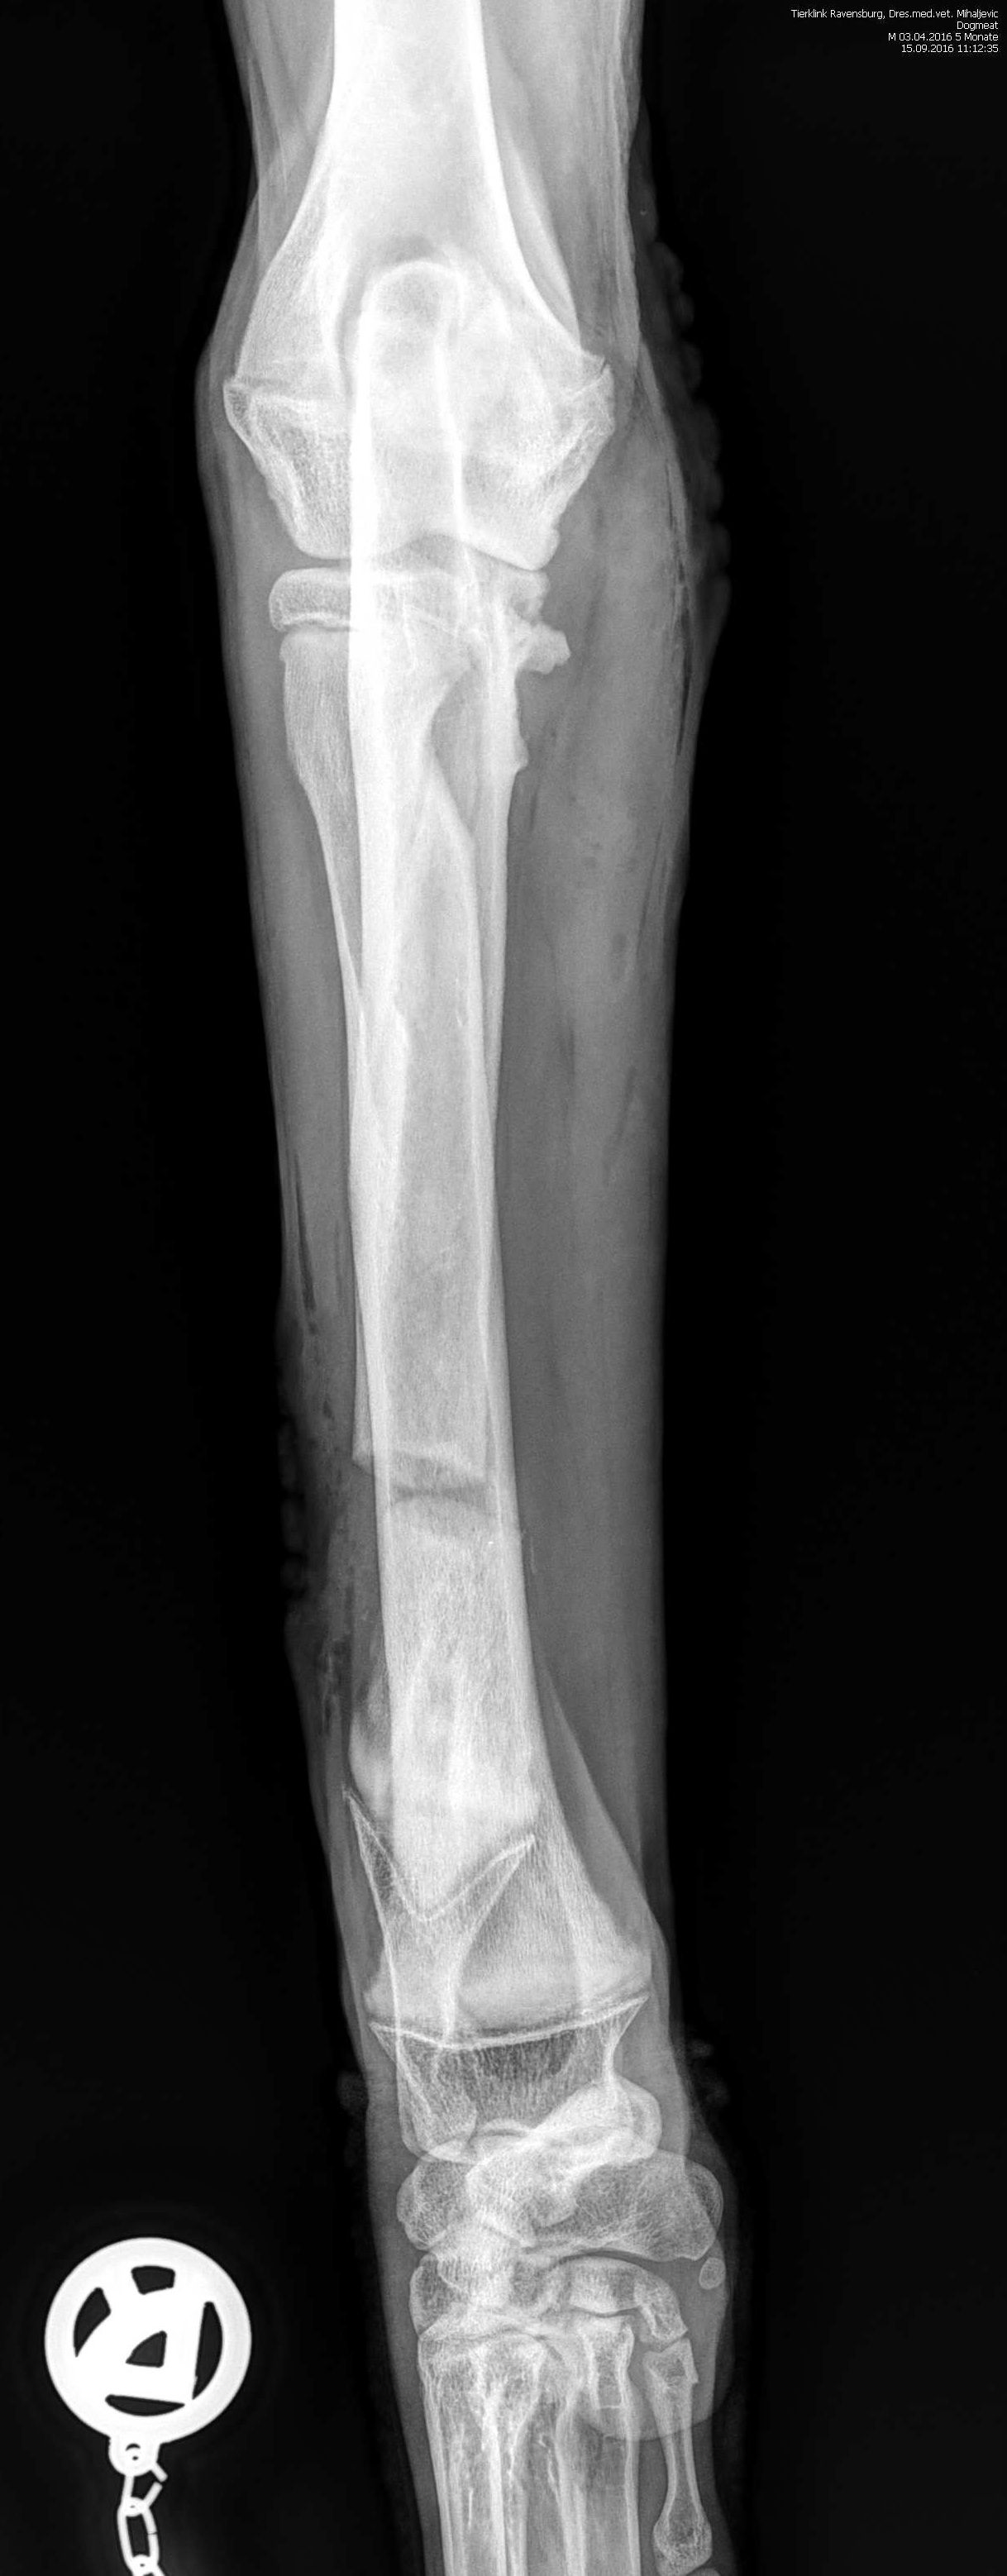

Sooo habe nun auch die Nachher Bilder ich stelle nochmal beide rein also vorher und nachher.

Da sieht man schön den Knochenbruch der Ulnaresektionsosteotomie. Sind aber wohl unterschiedliche Postionen vor und nach der OP der Aufnahmen

Auf dem oberen Bild sieht man deutlich das Fragment auf der rechten Seite das entfernt wurde. Selber am Gelenk hab ich es auch nur mit der Unterstützung vom Arzt gesehen. Also bei den seitlichen Aufnahmen da erkenne ich ohne Anleitung auch nichts. Die ct Aufnahmen checkt man auch nur mit Arzt Erklärung